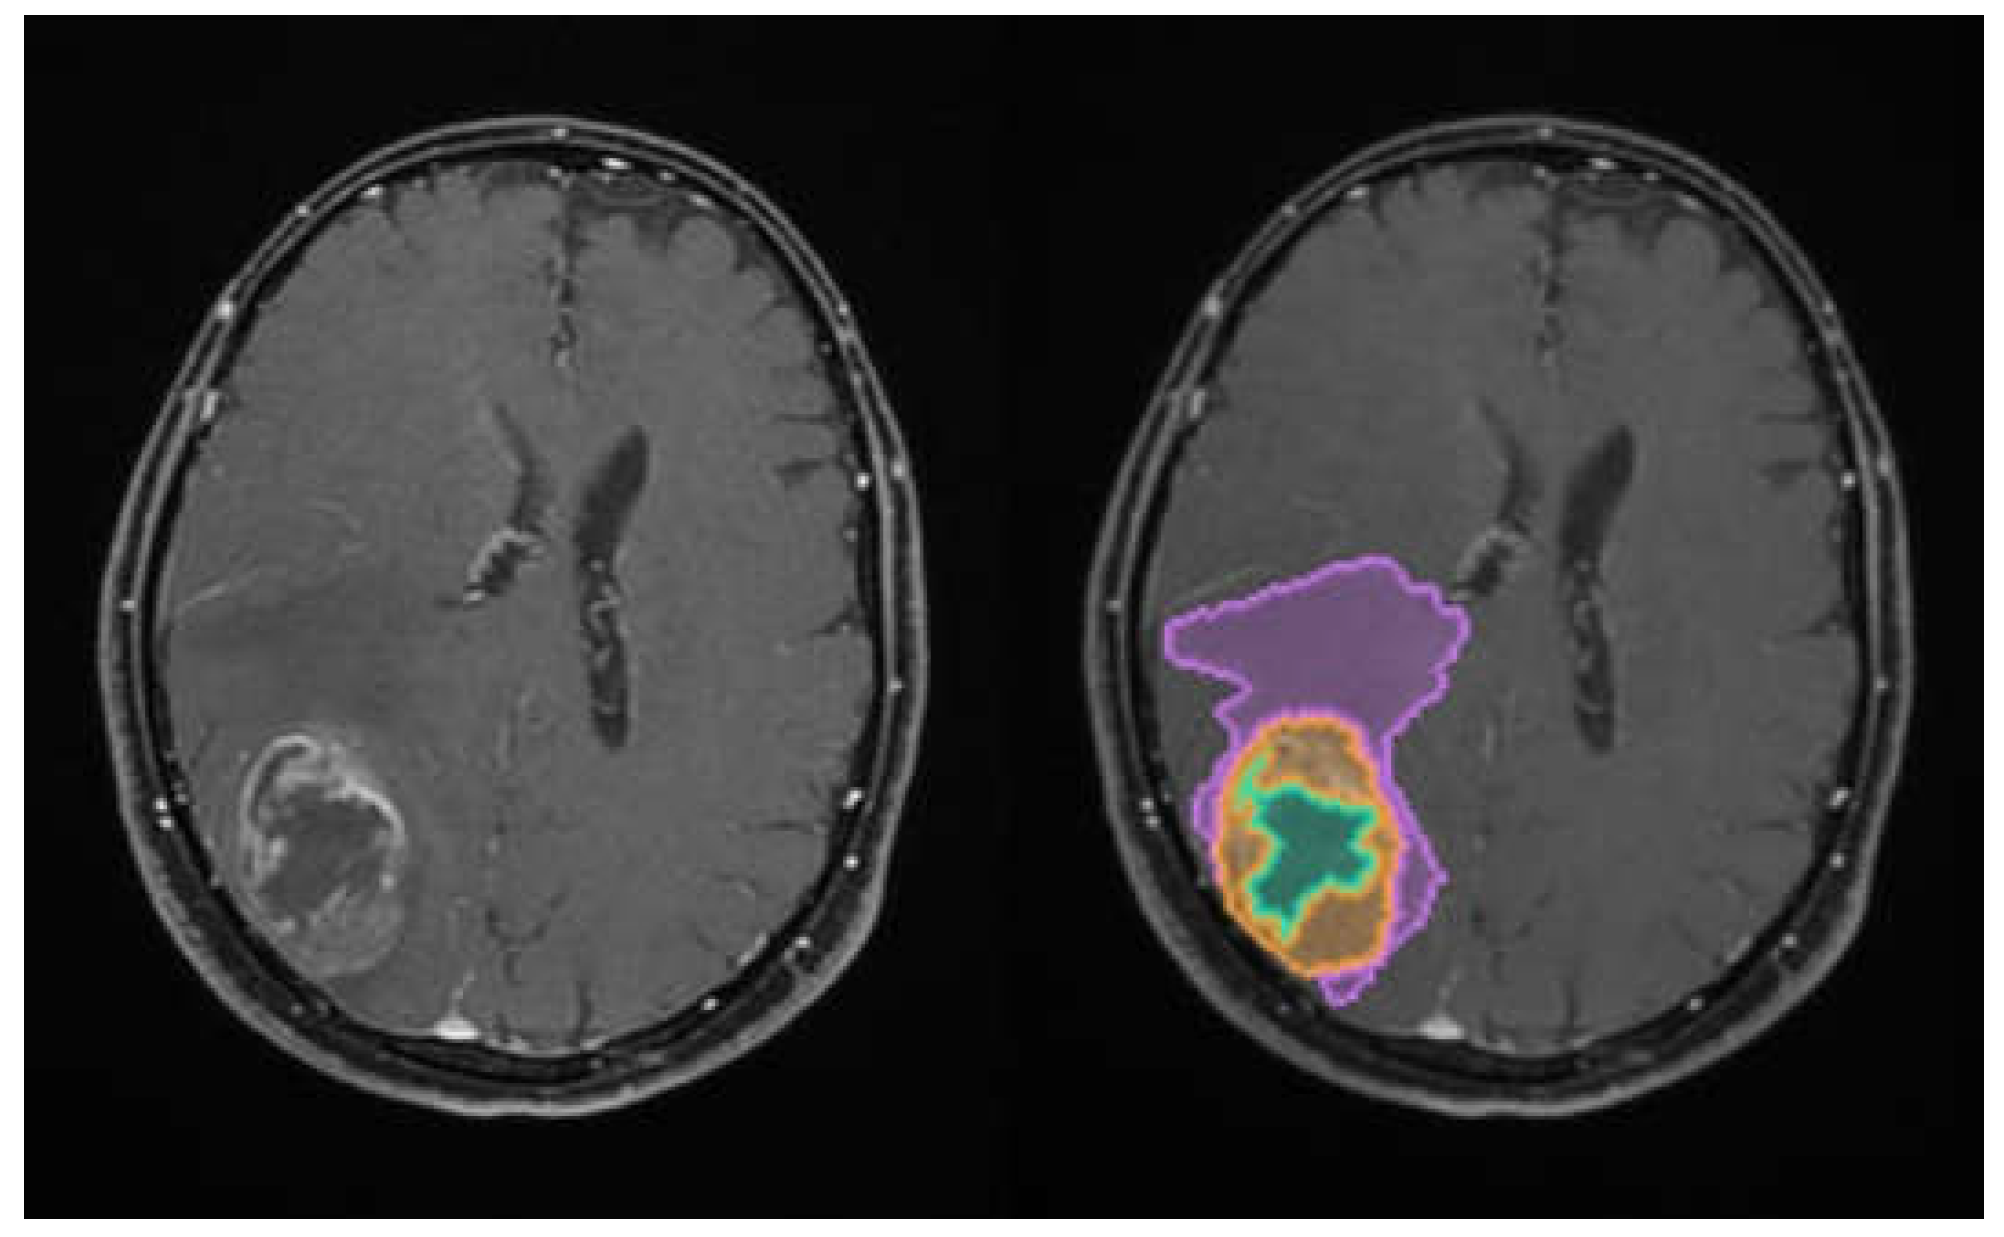

The total tumoral volume was thus partitioned into these three distinct sub-compartments, with the resulting Digital Imaging and Communication in Medicine (DICOM)-processed outputs illustrated in Figure 1.

Figure 1. Illustration of the automated volumetric analysis of contrast-enhanced T1-weighted axial MRI sequences using the mdbrain software (scale 1:20). The segmented regions include the necrotic core (green), the contrast-enhancing tumor component (orange), and the perilesional edema (purple) (approval was obtained from the Ethics Committee of the University of Medicine and Pharmacy “Grigore T. Popa” Iasi).